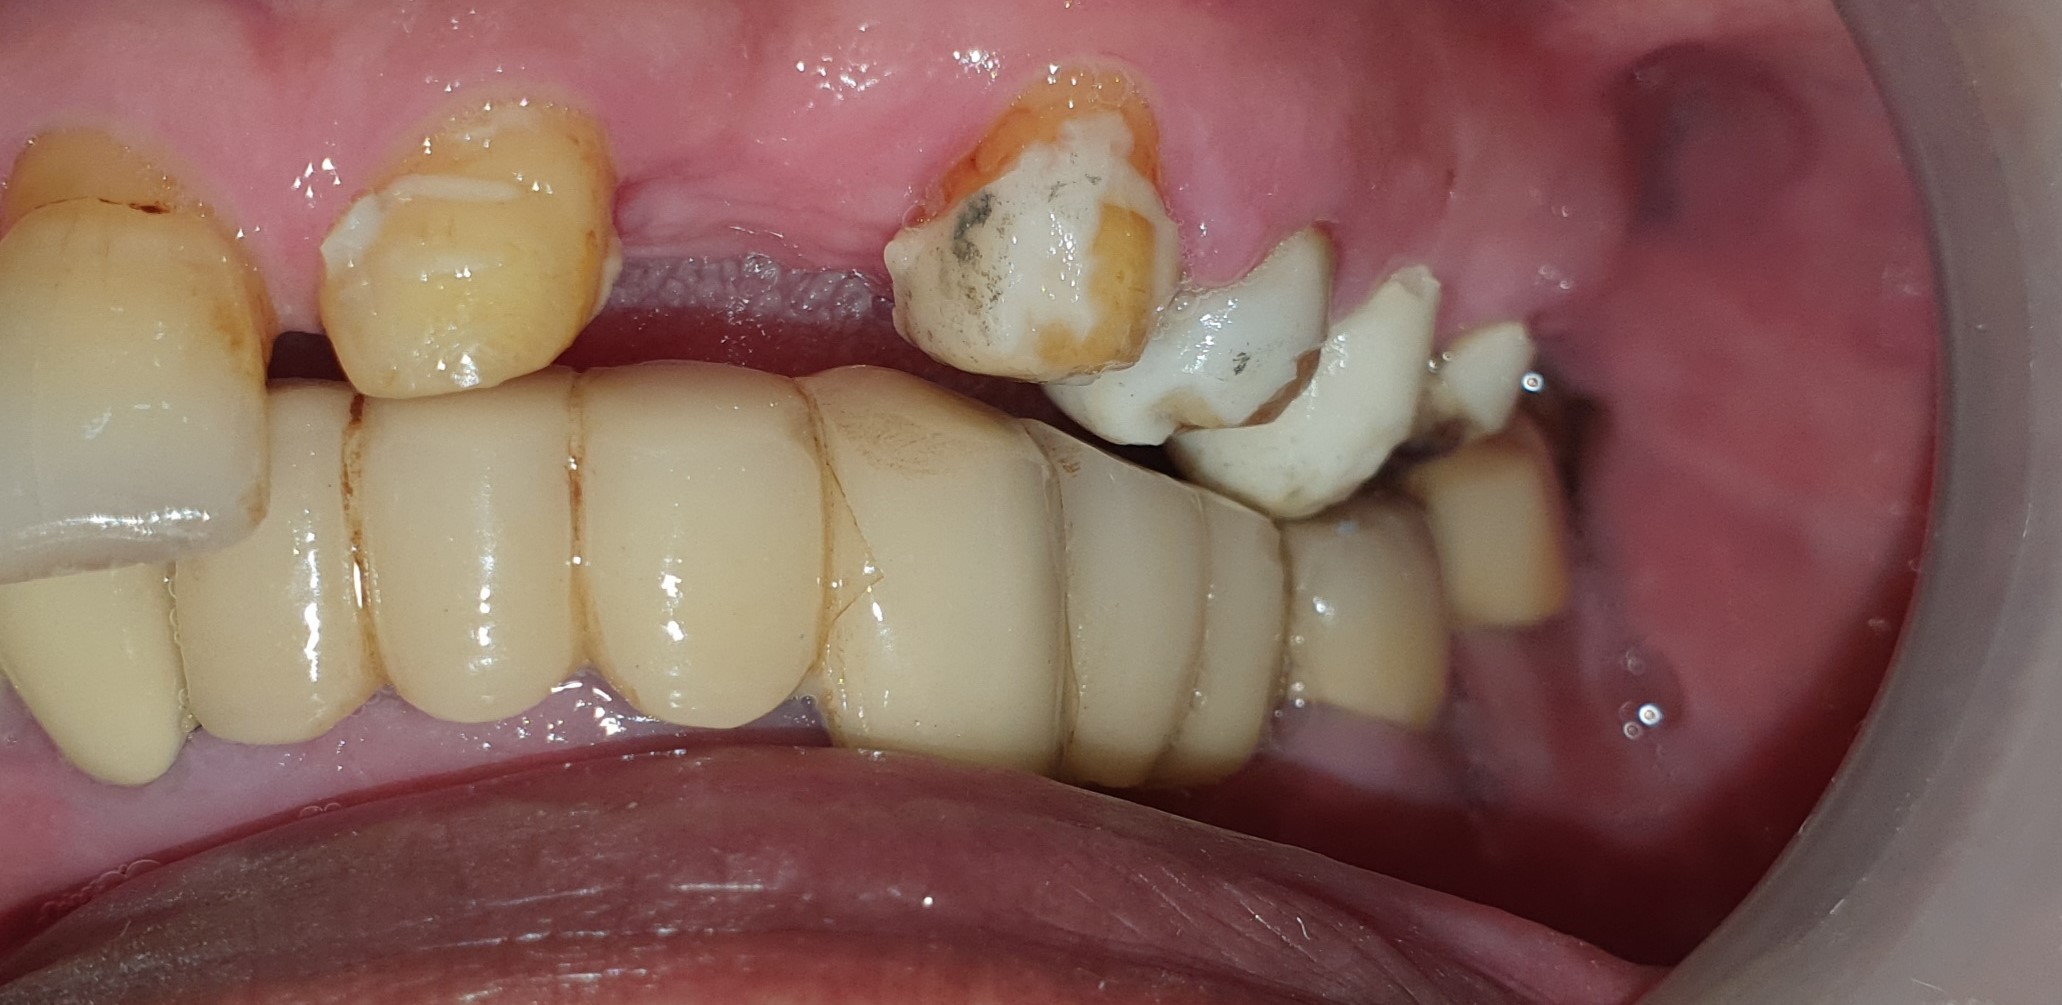

Tình trạng răng ban đầu

Hình ảnh răng hàm trên và dưới

Răng mock-up trên miệng – đồng thời là răng tạm trong quá trình chờ răng sứ